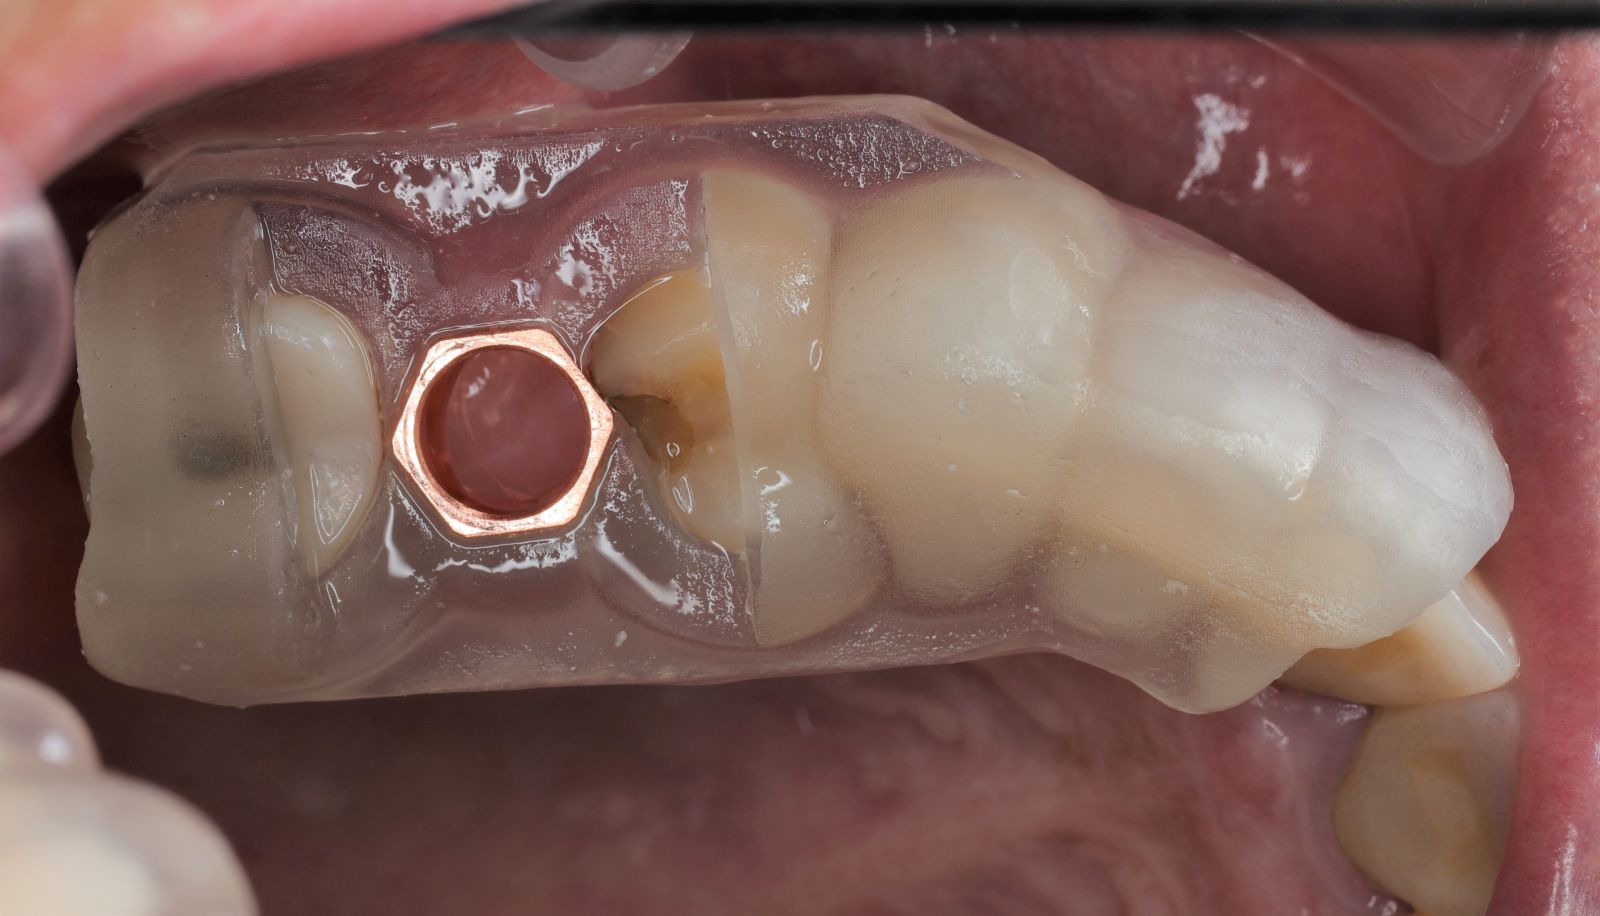

【 案 例 二】

- 手術過程,在植入植體前先用導板定位,確認植牙位置及角度。

- 手術中先使用導板定位,確認植牙角度及位置

- 藉由導板的定位,無須劃開傷口,精準的植入植體。

- 植入植體後不用劃開傷口無須縫合,鎖上癒合帽等待骨整合完成,過程輕鬆舒適。

- 3-4個用即可裝上全瓷牙冠恢復咬合功能